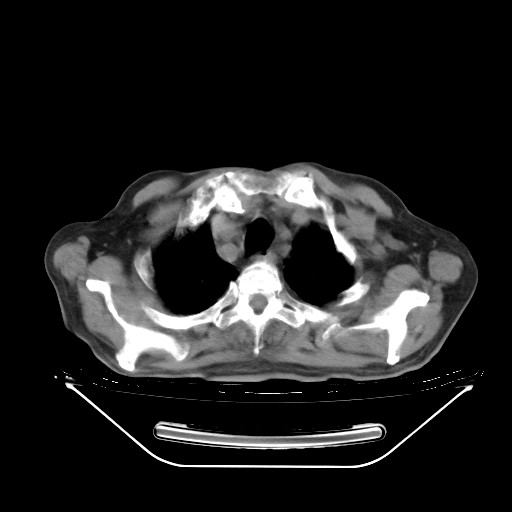

今天复查肺部CT,发现双肺广泛磨玻璃样改变。所以我把3月19日和5月9日相隔50天的肺部CT上传。请大家会诊。

2009年3月19日肺部CT片。

5月9日肺部CT(在4月27日齐鲁医院肺部CT描述部分肺组织磨玻璃样改变,12天后肺组织广泛磨玻璃样改变)